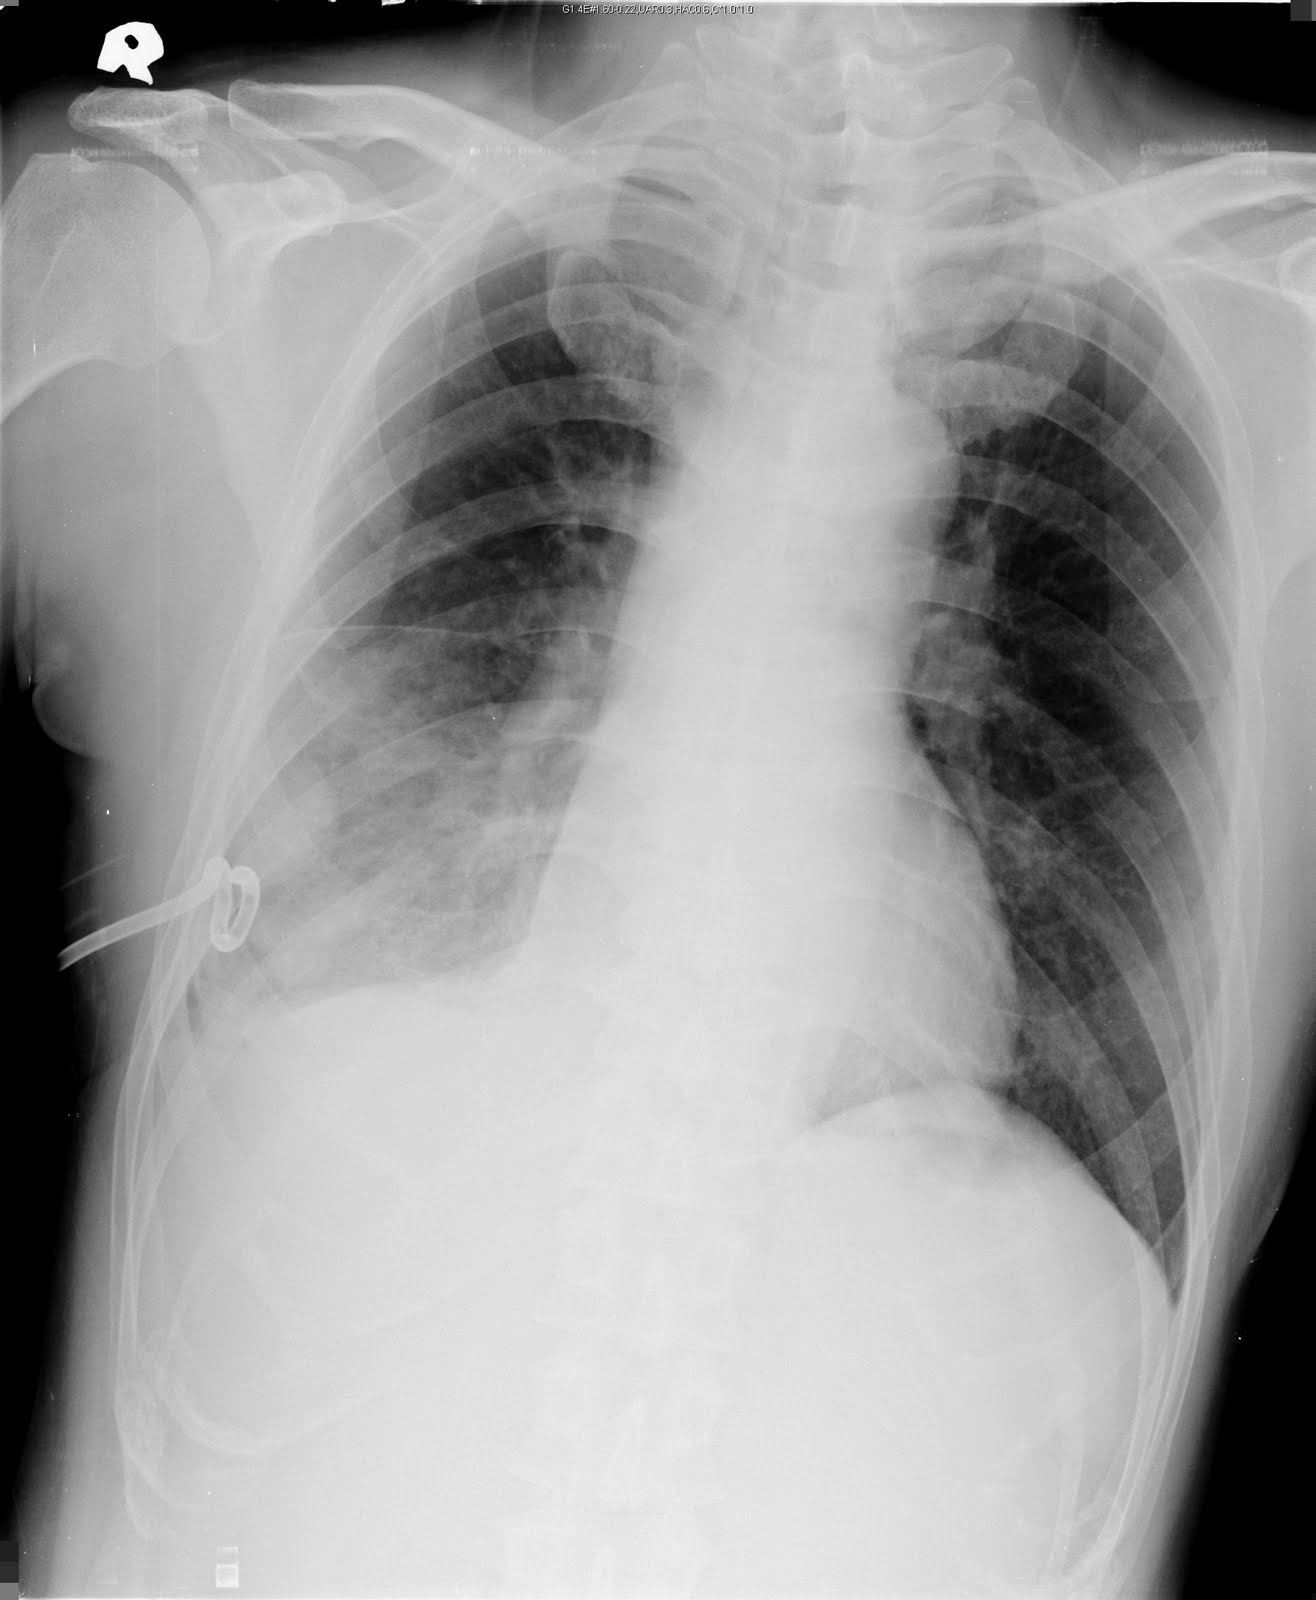

CXR 胸部x光判讀 pulmonary embolism

Left lung oligemia (Westermark sign)

pulmonary embolism in left pulmonary artery

1. Only 10% involve the upper lobe

2. pulmonary infarction 10-15%, wedge-shaped

3. Westermark’s sign (focal oligemia) Palla’s sign (prominent right descending pulmonary artery)

4. Pleural effusion

5. Elevated the diaphram

References: Radiology of Chest Diseases